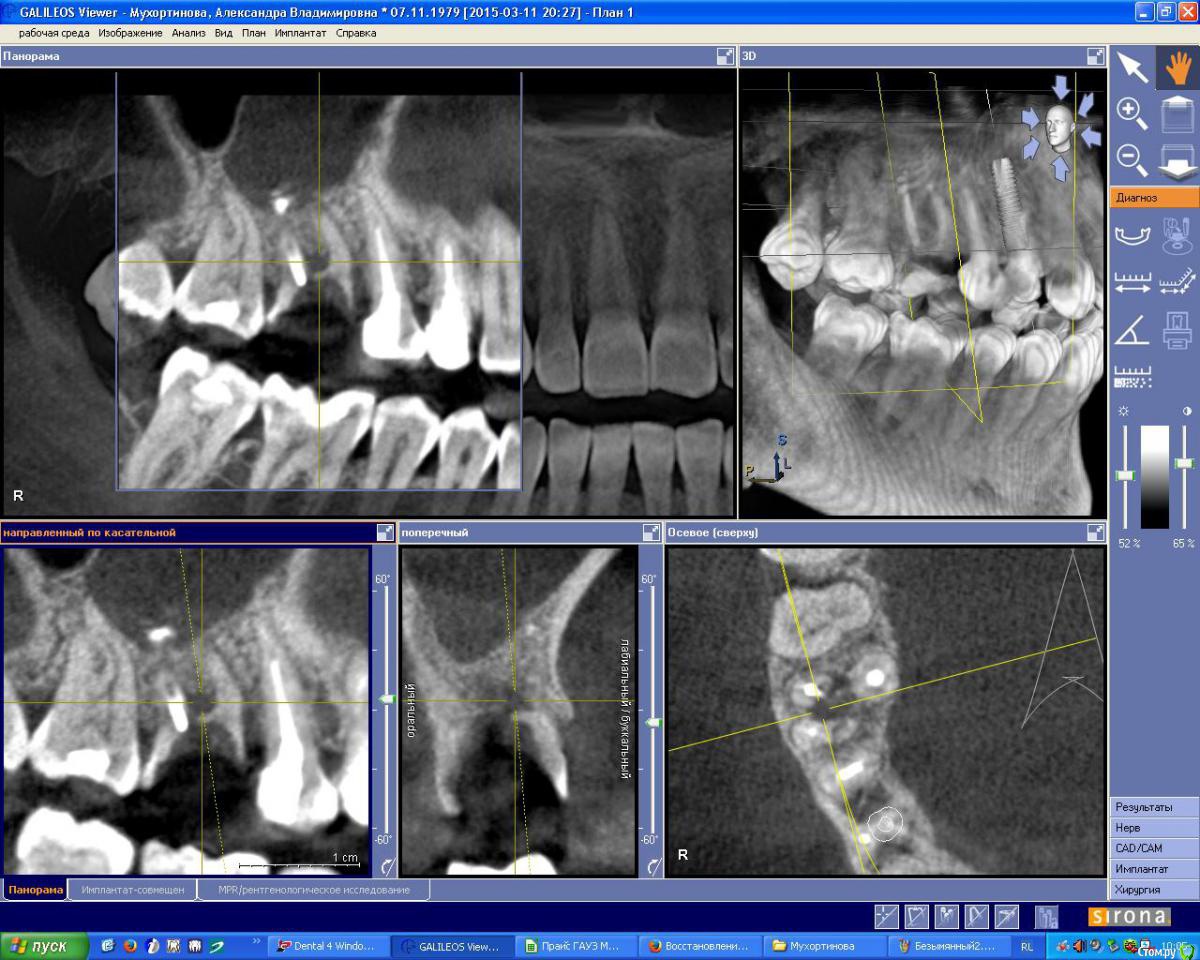

IshIm0 Опубликовано 8 июля, 2015 Поделиться Опубликовано 8 июля, 2015 (изменено) Добрый день. Пациентке Н. 2 недели назад ЛОР-врач удалил инородное тело из гайморовой пазухи справа (пломбировочный материал), который мигрировал в подглазничную область. Сейчас необходимо удалить зуб 16, пациентка хочет имплантат в последующем.Как всё правильно сделать ? Я думаю атравматично удалить зубик, аккуратно вычистить оставшийся пломбировочный материал в проекции дистально-щечного корня зуба 16 через лунку, подсыпать ксенокость, укрыть резорбируемой мембраной, через пол года установить имплантат в проекции 16 с одномоментным синус-лифтингом. Изменено 8 июля, 2015 пользователем IshIm0 Ссылка на комментарий

JIM Опубликовано 12 июля, 2015 Поделиться Опубликовано 12 июля, 2015 Пациентке Н. 2 недели назад ЛОР-врач удалил инородное тело из гайморовой пазухи справа (пломбировочный материал), который мигрировал в подглазничную область Что же ЛОР сказал об остальной части пазухи? Как-то по снимкам там не очень хорошо... Ссылка на комментарий

IshIm0 Опубликовано 16 июля, 2015 Автор Поделиться Опубликовано 16 июля, 2015 (изменено) Что же ЛОР сказал об остальной части пазухи? Как-то по снимкам там не очень хорошо...Снимки до операции у ЛОР врача, предполагаю, что на инородное тело так слизистая отреагировала, да и на инфицированный зубик. В итоге удалил зуб -> сгусткок -> тонкая коллагеновая губка -> X-образный фиксирующий губку шов.В бифуркации разрастание грануляционной ткани было.Всем спасибо за советы. Изменено 16 июля, 2015 пользователем IshIm0 Ссылка на комментарий